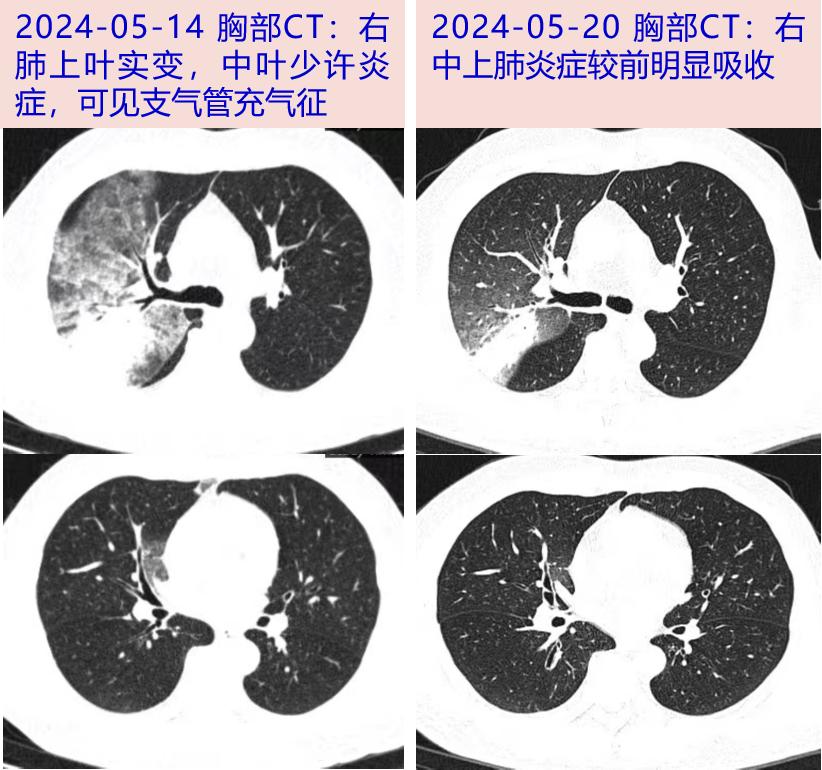

2024-05-14 仍有高热,Tmax 39℃,伴干咳,咳黄粘痰。到我院门诊查看WBC 6.07×109/L,N 70.6%,LY 21.2%;hsCRP 102.2mg/L。胸部CT平扫:右上肺大片实变,内见支气管充气征。中山医院感染科为明确肺炎病因,2024-05-15收益。

2024-5-20 体温平整,乏力好转,无干咳、咳痰,复查WBC。 3.6×109/L,N 59.1%,L 1.1×109/L;hsCRP 36.5mg/L,ESR 28mm/h,PCT 0.04ng/mL,ALT/AST 32/28U/L,Alb 35g/L,NT-proBNP 290pg/mL。hsCRP、AST、NT-proBNP较前降低,淋巴细胞计数,Alb较前升,胸部CT:右肺上叶发炎,比05-14明显吸收,出院。